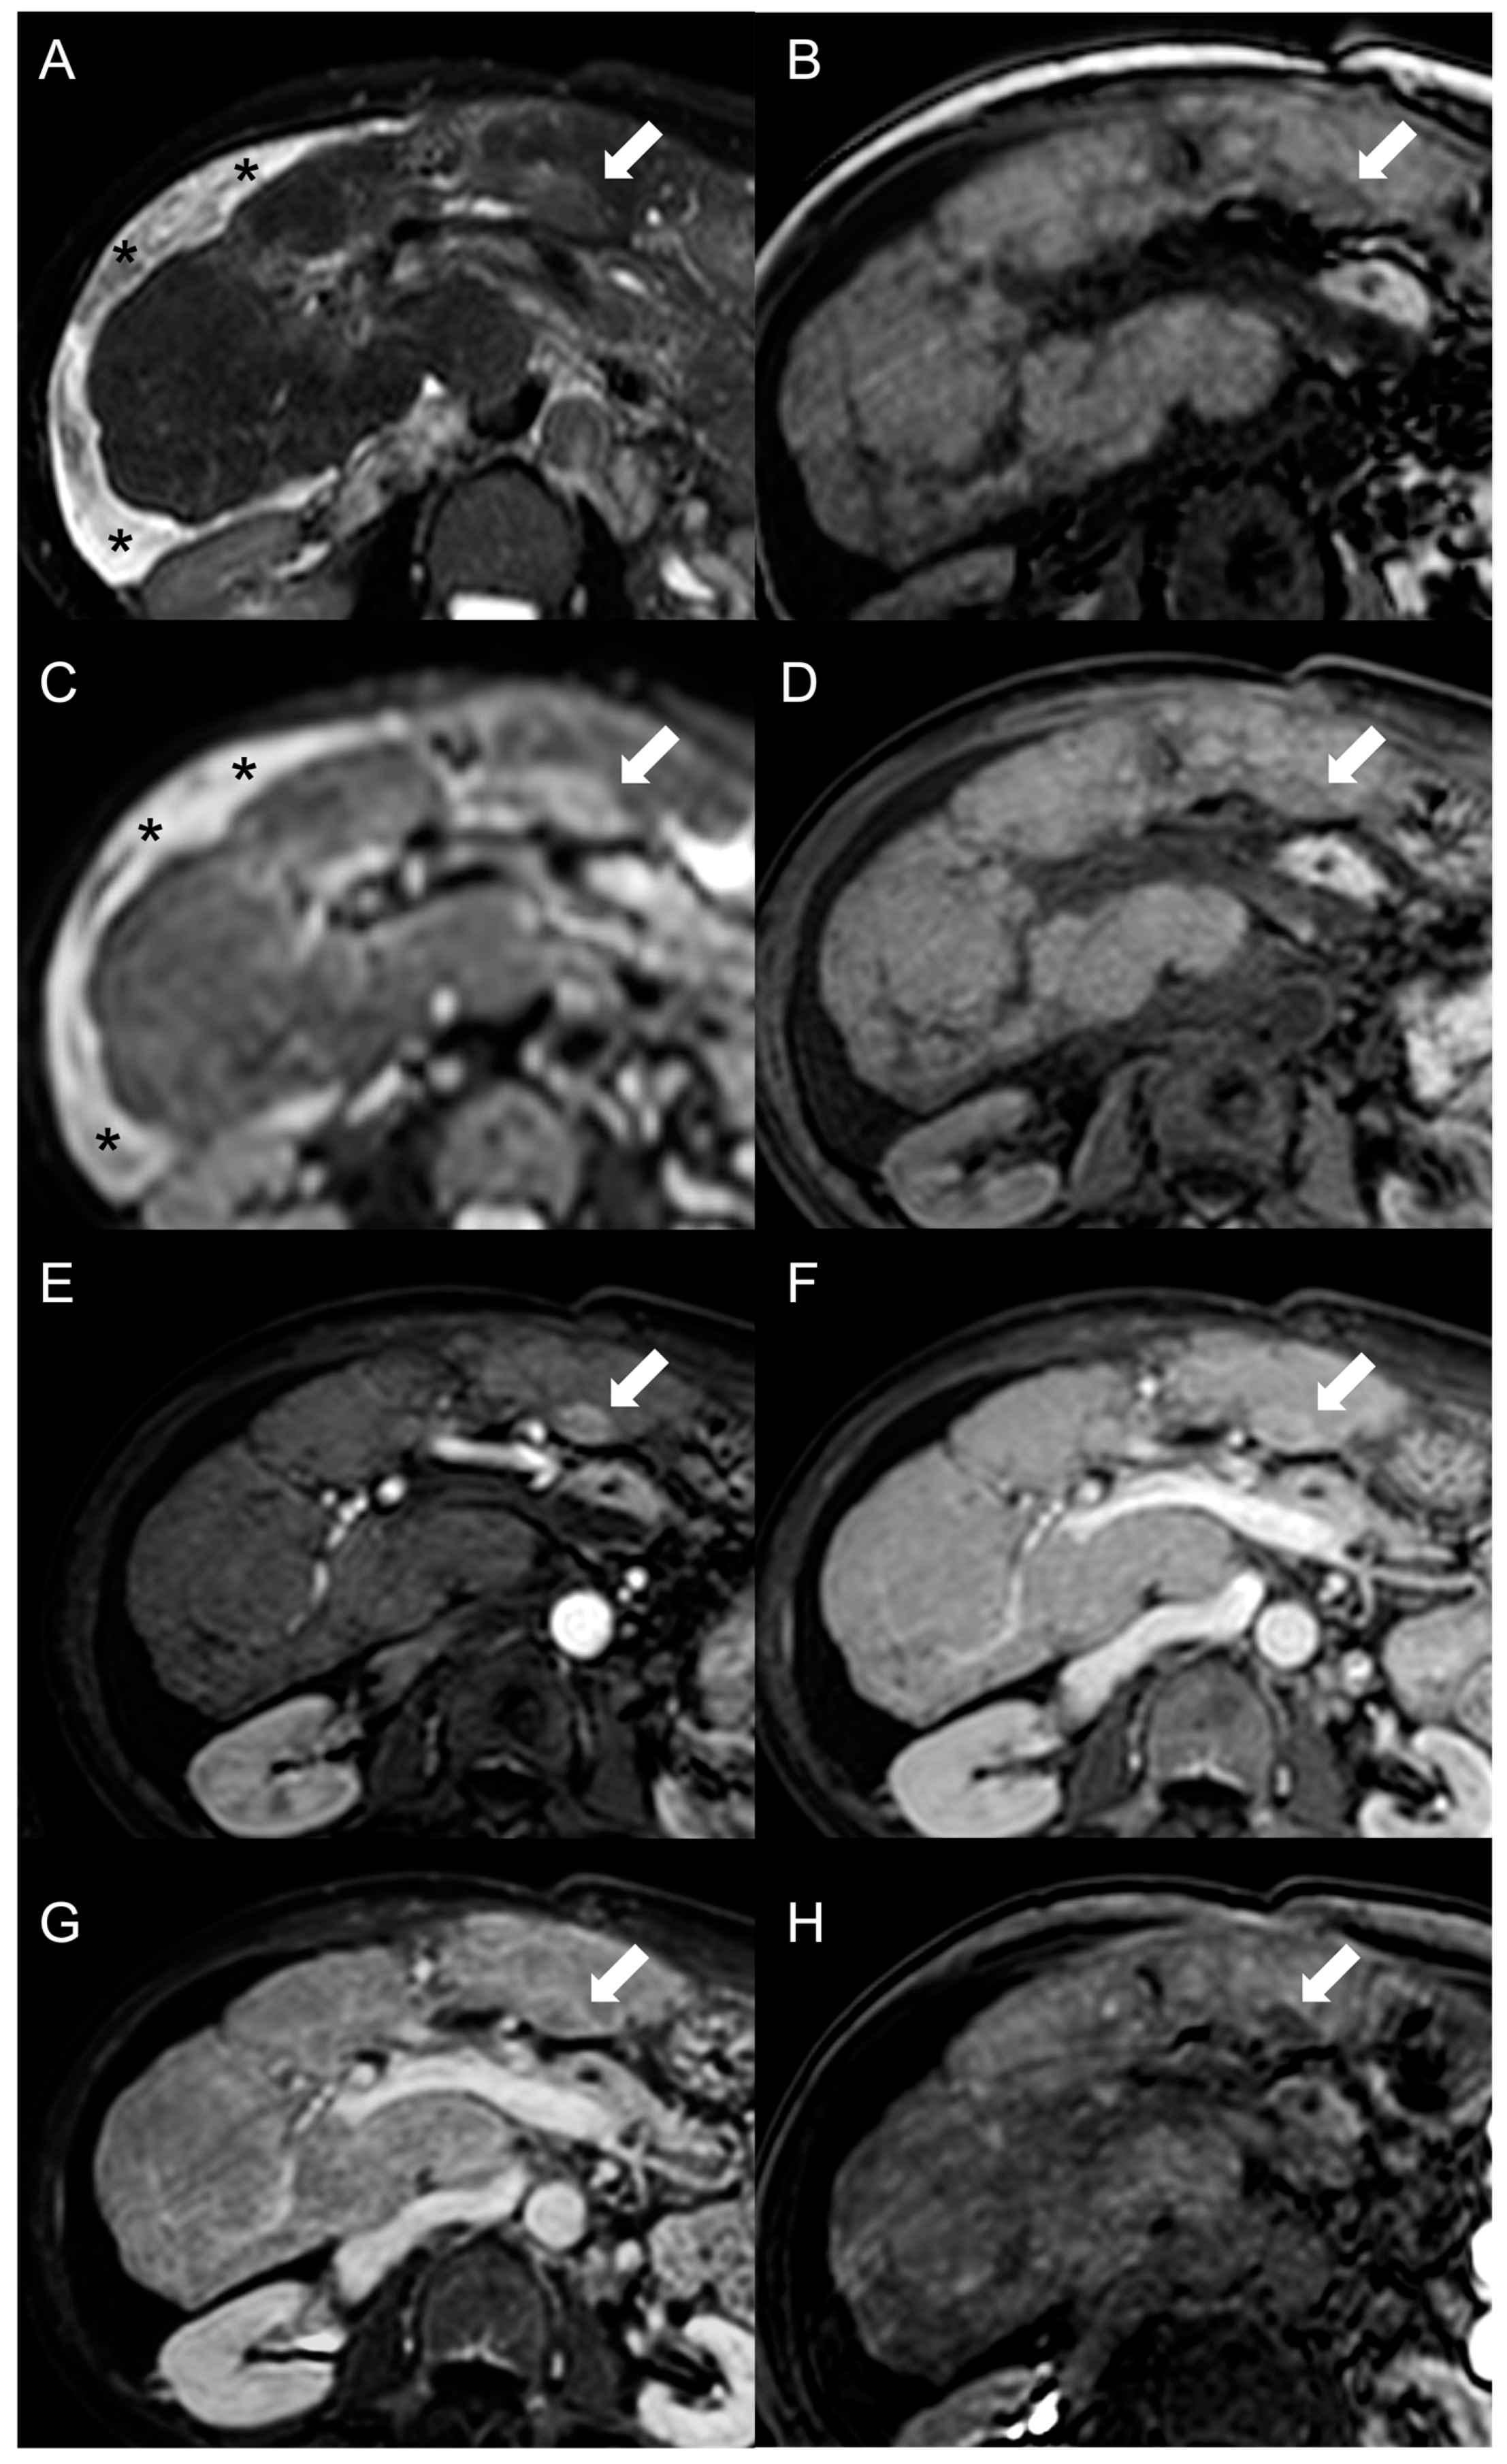

However, considering that approximately 25% of HCCs do not display washout in the portal and delayed phases, while up to one-third of FNH-like RNs can show it, the specificity of this feature for the diagnosis of HCC in BCS is relatively low. As reported by Van Wettere et al. [22], the association of homogeneous APHE and homogeneous washout was identified in one-third of benign lesions and in half of HCC cases. The resulting sensitivity and specificity for diagnosing HCC were 50% and 70%, respectively. When considering the combination of any type of APHE (homogeneous, peripheral or central) and any type of washout (homogeneous or peripheral), a sensitivity of 100% and a specificity of 61% were achieved. For this reason, given the risk of an unacceptable rate of false-positive results, the LI-RADS and AASLD/EASL criteria for the non-invasive diagnosis of HCC cannot be applied in BCS patients [28,29,30]. The differential diagnosis between FNH-like RNs and HCC becomes even more challenging due to the potential for the former to increase in size and/or in number. Therefore, it is important to consider additional features supportive of diagnosis of HCC, such as T1 hypointensity, hyperintensity in T2-weighted and high b-value DWI, and absence of a central scar on MRI [42], as shown in Figure 6.

Figure 6.

MRI examination of a 67-year-old female patient with Budd–Chiari syndrome reveals a new focal lesion of 13 mm in the left lobe (arrow). The lesion appears hyperintense on T2-weighted images (A), hypointense on T1-weighted images (B,D) and shows restricted diffusion in high-b-value DWI (C). After contrast agent administration, the lesion demonstrates marked enhancement on T1-weighted arterial phase images (E), followed by central washout with enhancing capsule on T1-weighted portal venous (F) and delayed (G) phases. On T1-weighted images in the hepatobiliary phase (H) the lesion shows a hypointense signal, suggesting a diagnosis of HCC. Perihepatic ascites (asterisks) can be observed on T2-weighted images (A) and DWI (C).

Hepatobiliary contrast agents provide valuable help in the differential diagnosis, as HCC most often demonstrates a hypointense signal in HBP. In the above-mentioned study [22], the combination of this feature with APHE and washout proved effective in distinguishing all HCC lesions from FNH-like RNs. Indeed, benign regenerative lesions typically appear isointense-to-hyperintense compared to the normal liver in HBP, regardless of the presence of washout on portal venous or delayed phase images.

Hemangioma, true focal nodular hyperplasia, adenoma, dysplastic nodule, and necrotic regenerative nodule are other focal liver lesions that may coexist in patients with BCS (Figure 7).

Figure 7.

MRI examination of a 49-year-old female patient with Budd–Chiari syndrome reveals multiple lesions, including two large FNH-like RNs (arrows) in V-VI liver segment. On fat-saturated T2-weighted images (A), these nodules are iso-hypointense with an inhomogeneous central hyperintensity and a low-signal perinodular rim. On T1-weighted images (B) the FNH-like RNS appear hyperintense, one of them exhibiting a central hypointensity corresponding to the central scar. In DWI (b-value = 600) (C), they show the same signal intensity as the adjacent liver parenchyma, with appreciable low-signal peripheral rim. On T1-weighted unenhanced (D), arterial (E), portal (F), and delayed (G) phase images, the FNH-like RNs demonstrate inhomogeneous arterial enhancement and isointense signal on the portal and delayed phases; the hypointense perinodular rim, representing congested hepatic tissue, remains noticeable. In the hepatobiliary phase (H), the FNH-RNs display inhomogeneous iso-hyperintense signals compared to the surrounding liver parenchyma. A third lesion, compatible with a hemangioma (arrowhead), is also visible, showing homogeneous hyperintensity on fat-saturated T2-weighted images (A) and DWI (b-value = 600) (C), hypointensity on T1-weighted images (B), slow centripetal globular enhancement on arterial (E), portal (F), and delayed phase (G) images, and hypointense signals in the hepatobiliary phase (H).